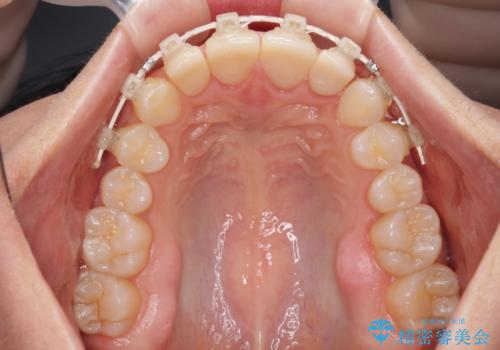

下顎前歯は空隙歯列弓であったので、アンカースクリューとワイヤー装置を用いてスペースを閉じていくこととし、上顎前歯は矯正治療用の仮歯に置き換えた上で、仮歯の大きさを削って小さくしながら、上下前歯部の部分矯正を行うこととしました。

日本と海外を拠点に仕事をされていらっしゃるため、数ヶ月治療があいてしまうことがあり、期間はかかりましたが、2年間で望み通りの前歯に仕上げることができました。